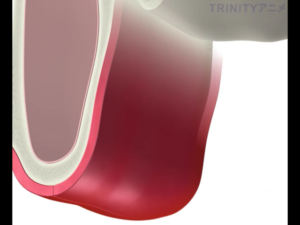

下の図のように上顎の骨が少なく、副鼻腔との距離が近く骨を盛り上げる場合に選択する治療方法です。

歯茎を切開し、副鼻腔につながる骨を一部削除します。

副鼻腔内の粘膜を破らないように慎重に上方に持ち上げていきます。

それによってできた副鼻腔内の空洞に人工骨を填入します。

骨を盛り上げた部分にインプラントを埋入します。

この人工の骨が既存の骨と一体化するまで待機します。